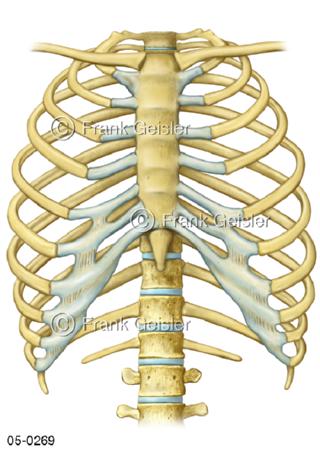

Bildergalerie Skelettsystem

Bilder zum Skelettsystem zeigen die Stützstruktur des menschlichen Körpers, die Knochen, eine besonders harte Form des Bindegewebes und Stützgewebes, welche das menschliche Skelett bildet, die Knochen des Stammes, der Extremitäten sowie der Gelenke